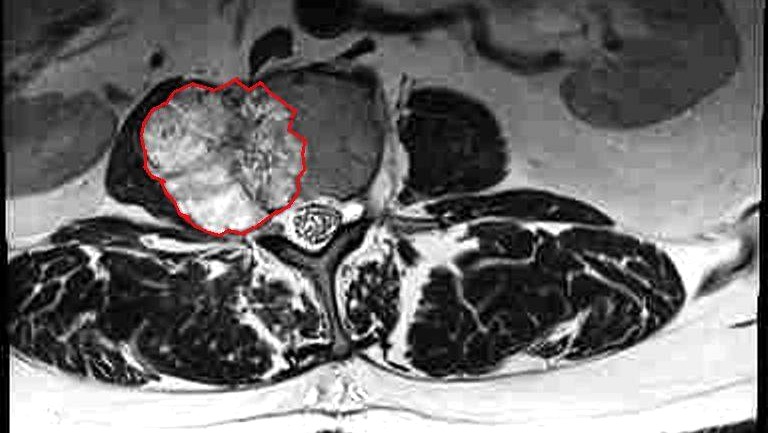

My friends. It seems that life is kicking my ass. I have a malignant (chordoma) tumor on my L2 vertebra. It's big and ugly and it is causing so much pain that I can no longer walk. I can't stand longer than a few seconds, maybe a minute, before I have to sit down.

This is a very rare cancer and there aren't any curative therapies. It is slow growing so - hopefully - after removal and post-operative recovery I can live a few years in peace. My workplace is giving me FMLA for the recovery period, but as many of you know, FMLA is UNPAID after your sick time and vacation pay are spent.